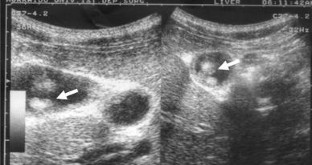

Fig. 2